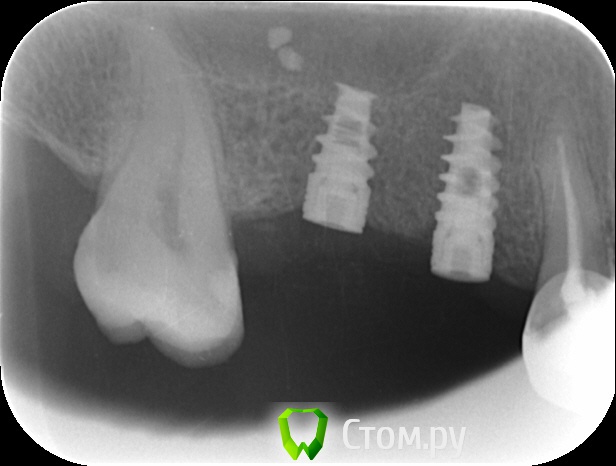

an_ver Опубликовано 12 сентября, 2014 Автор Поделиться Опубликовано 12 сентября, 2014 Вот снимки Ссылка на комментарий

an_ver Опубликовано 12 сентября, 2014 Автор Поделиться Опубликовано 12 сентября, 2014 На момент установки Ссылка на комментарий

k.t.m. Опубликовано 12 сентября, 2014 Поделиться Опубликовано 12 сентября, 2014 длина имплантата 6мм или ракурс такой? Ссылка на комментарий

an_ver Опубликовано 12 сентября, 2014 Автор Поделиться Опубликовано 12 сентября, 2014 (изменено) длина имплантата 6мм или ракурс такой?Не, 8 мм.У Альфы на станд.платформе нет 6 мм,только на широкой Изменено 12 сентября, 2014 пользователем an_ver Ссылка на комментарий